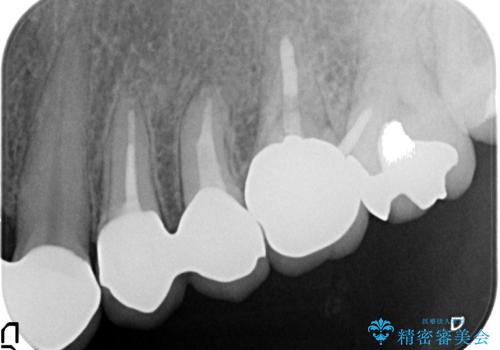

左上4、5番目の歯は根尖病変を認めたため再根管治療を行い、オールセラミッククラウンによる補綴を行いました。

今回用いたオールセラミッククラウンは、ジルコニアフレームという白い素材の上にセラミックを盛っているため審美性が非常に高いのが特徴です。

またジルコニアは人工ダイヤモンドの材料にも使われているほど高い強度を持っており、そのためオールセラミッククラウンは審美性だけでなく、奥歯やブリッジの補綴も可能とするクラウンです。